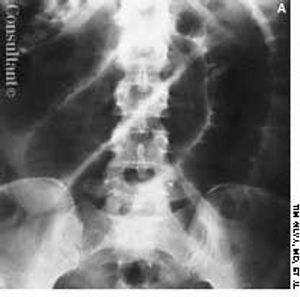

Cough, fever, diarrhea, and weight loss had disturbed a 52-year-old woman for 1 month. AIDS had been diagnosed 5 years earlier, but she had declined medical treatment. The patient's vital signs were stable when she was admitted to the hospital. Physical examination results were unremarkable except for thrush and mild, diffuse abdominal tenderness.